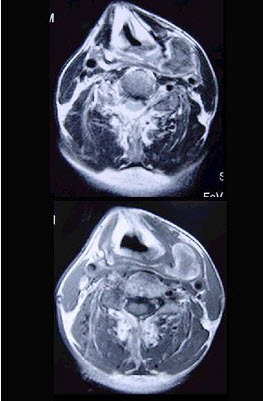

男性,40岁,发现左侧颈部小包块,CT、MRI检查如图所示,请选择最可能的诊断()。

A、神经鞘瘤

B、神经纤维瘤

C、海绵状血管瘤

D、肿大淋巴结

E、副神经节瘤

C